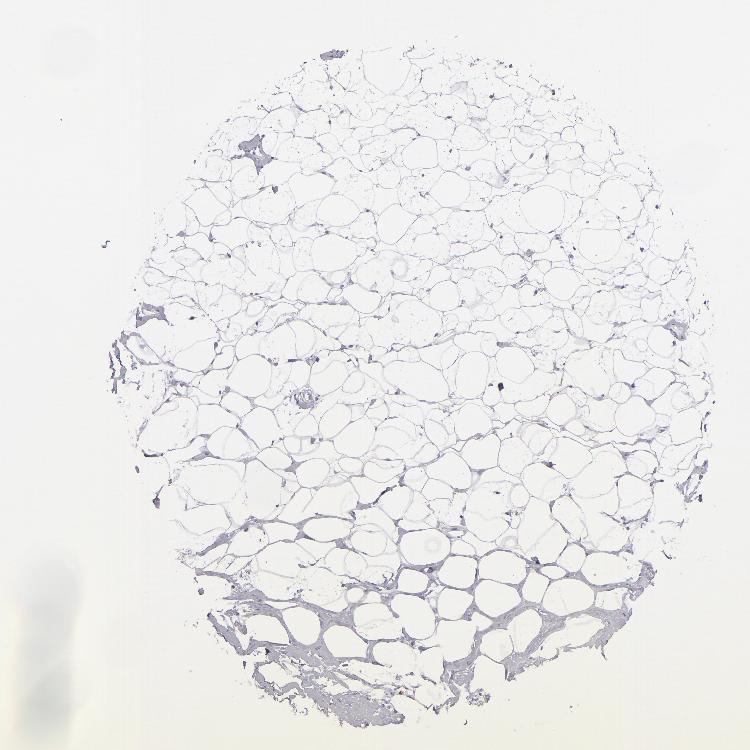

TISSUE PRIMARY DATA BREAST Show tissue menu

BREAST - Antibody stainingi

Antibody staining in the annotated cell types in the current human tissue is reported as not detected, low, medium, or high, based on conventional immunohistochemistry profiling in selected tissues. This score is based on the combination of the staining intensity and fraction of stained cells.

Each image is clickable and will lead to virtual microscopy that enables deeper exploration of all samples and also displays staining intensity scores, fraction scores and subcellular localization as well as patient and tissue information for each sample.

Antibody HPA006884Antibody HPA006885Antibody CAB002452

Adipocytes Not detectedNot detectedNot detected

Glandular cells LowNot detectedNot detected

Myoepithelial cells Not detectedNot detectedNot detected